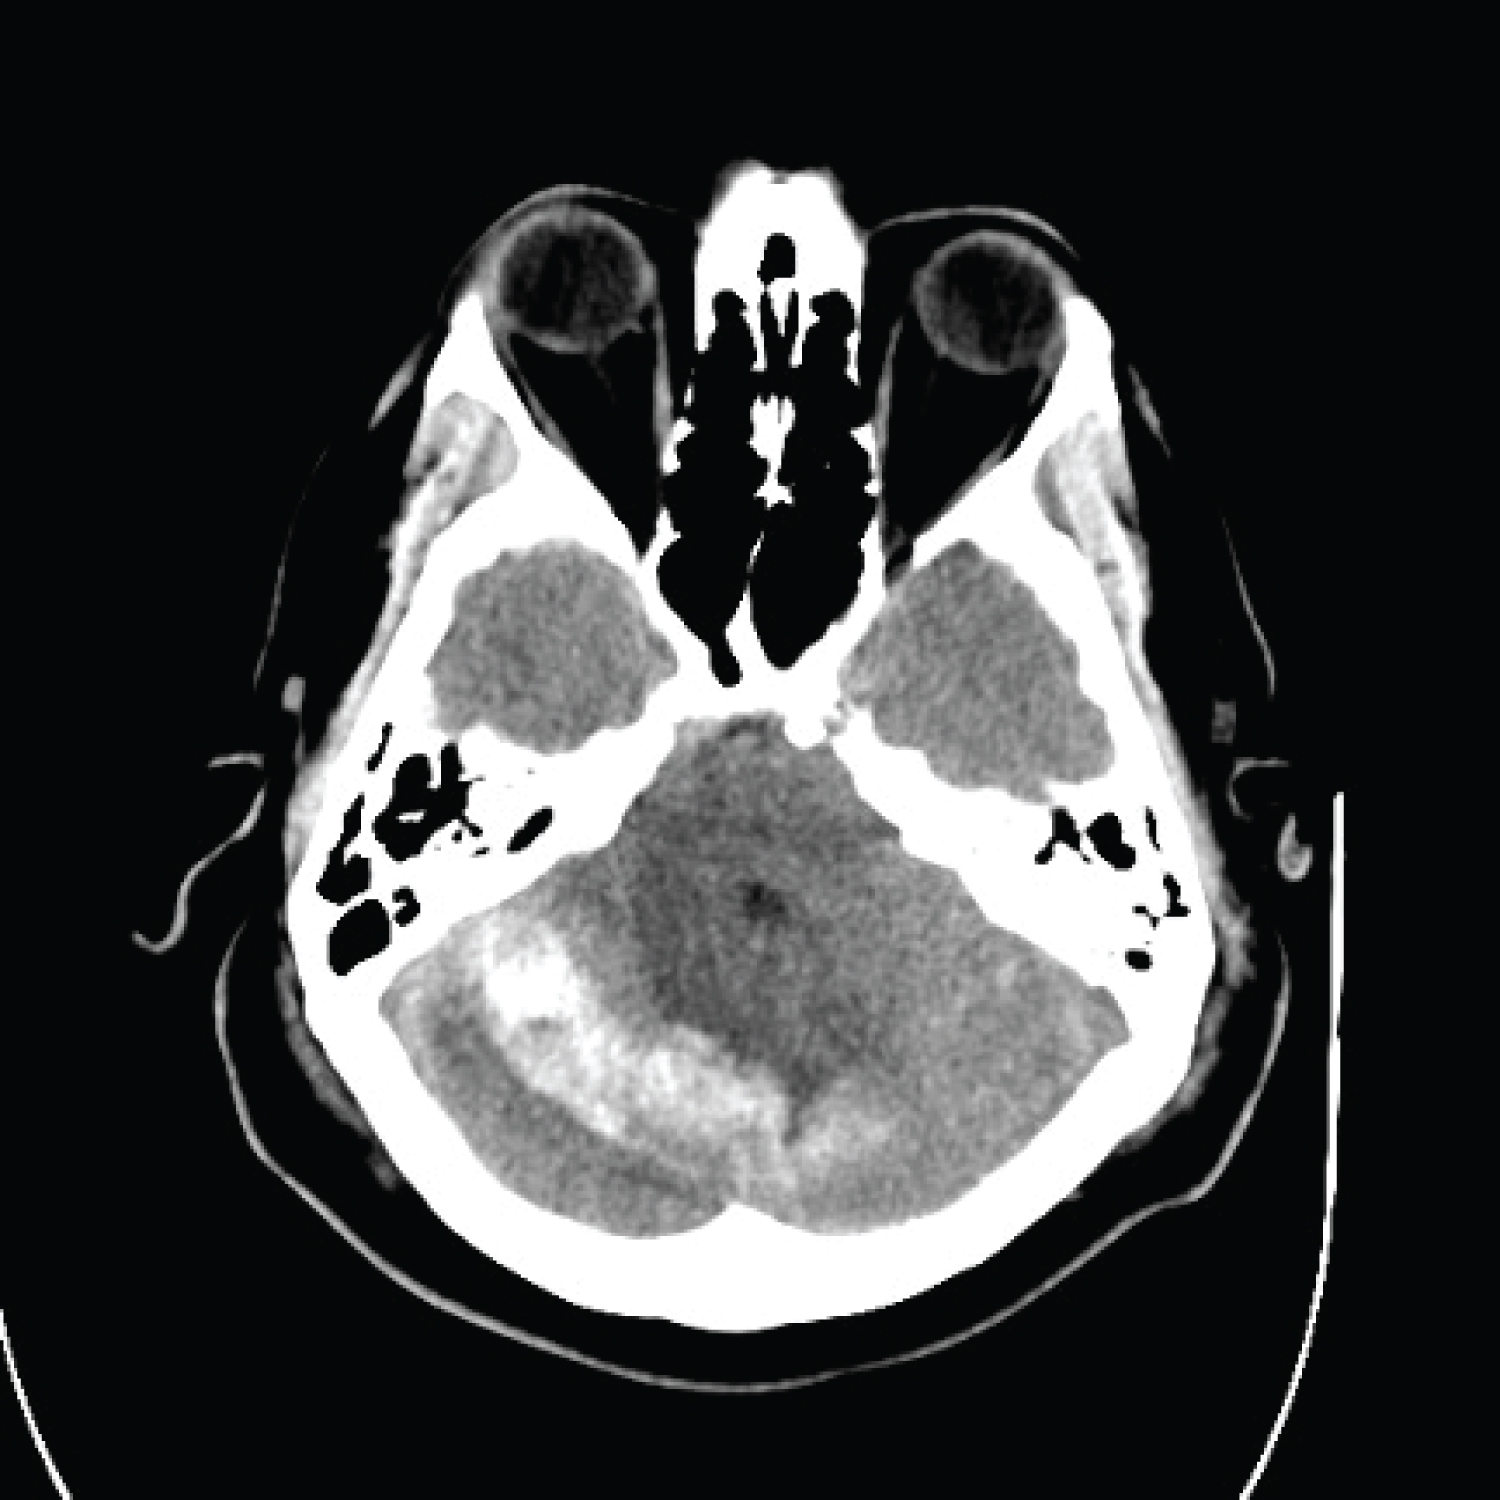

On POD4, a fever of 38.5 °C prompted the medicine consult team to order a non-contrast head computed tomography (CT) scan, suspecting meningitis. By POD5, the patient's condition had progressed to lethargy, although he remained arousable to verbal stimuli with intact motor strength. The CT scan revealed an acute right cerebellar parenchymal hemorrhage measuring 1.7 cm × 4.9 cm × 1.5 cm with mass effect and obstructive hydrocephalus, leading to an intracerebral hemorrhage (ICH) score of 1 (Figure 1). Despite the patient's lethargy and a GCS of 14, he maintained full orientation with a mild delay in verbal responses.

Figure 1: Head CT without IV contrast POD5 demonstrating a 1.7 cm × 4.9 cm × 1.5 cm right cerebellar hemorrhage with mild mass effect on the fourth ventricle. View Figure 1